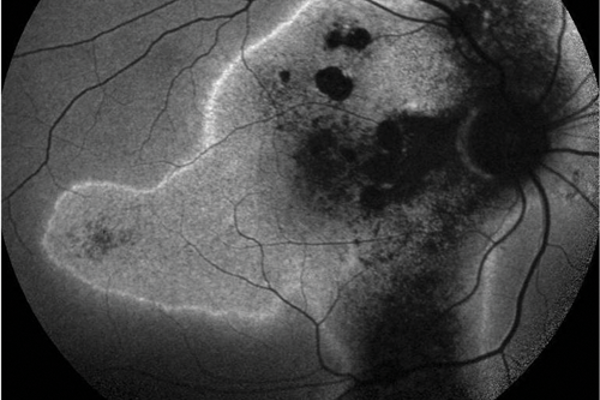

The management of chronic central serous chorioretinopathy